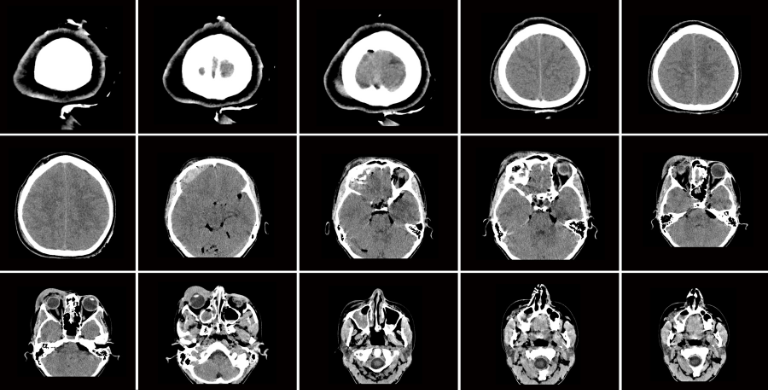

Cerebrovascular disease: what you need to know

Cerebrovascular disease refers to a group of conditions that affect the blood vessels and blood flow in the brain.